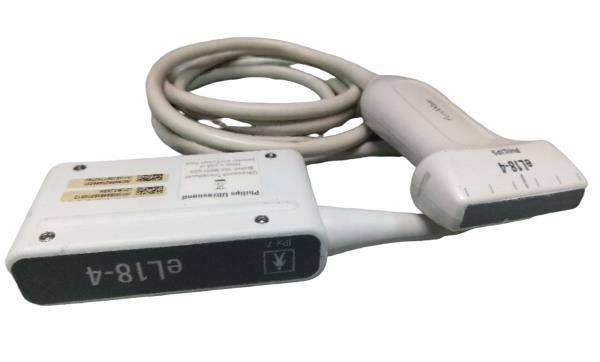

- Convex Probe: 3.5MHz-5MHz

- Elements: 128